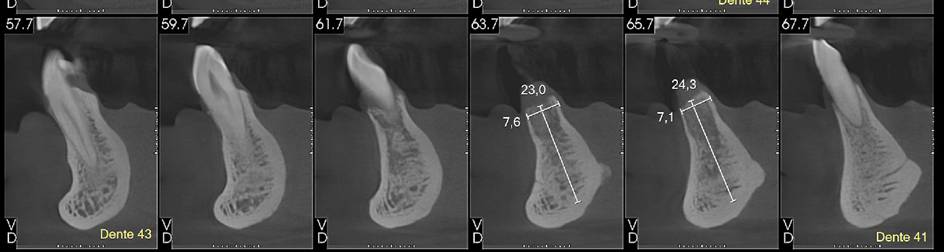

Avaliamos o espaço mésio-distal entre os dentes 33 e 43 e constatamos a ausência de distância para a colocação de implantes individualizados. Assim sendo, optamos pela instalação de dois implantes Veloce CM de diâmetro 3.3 e pilares do tipo micro-cônico para a solução clínica.

Dessa forma, na matéria desta semana, será abordada uma situação clínica de espaço mésio-distal restrito com o uso de implantes híbridos do tipo Veloce CM estreitos de 3.3 de diâmetro e posterior confecção de prótese sobre implantes com pilares intermediários do tipo micro-cônico.